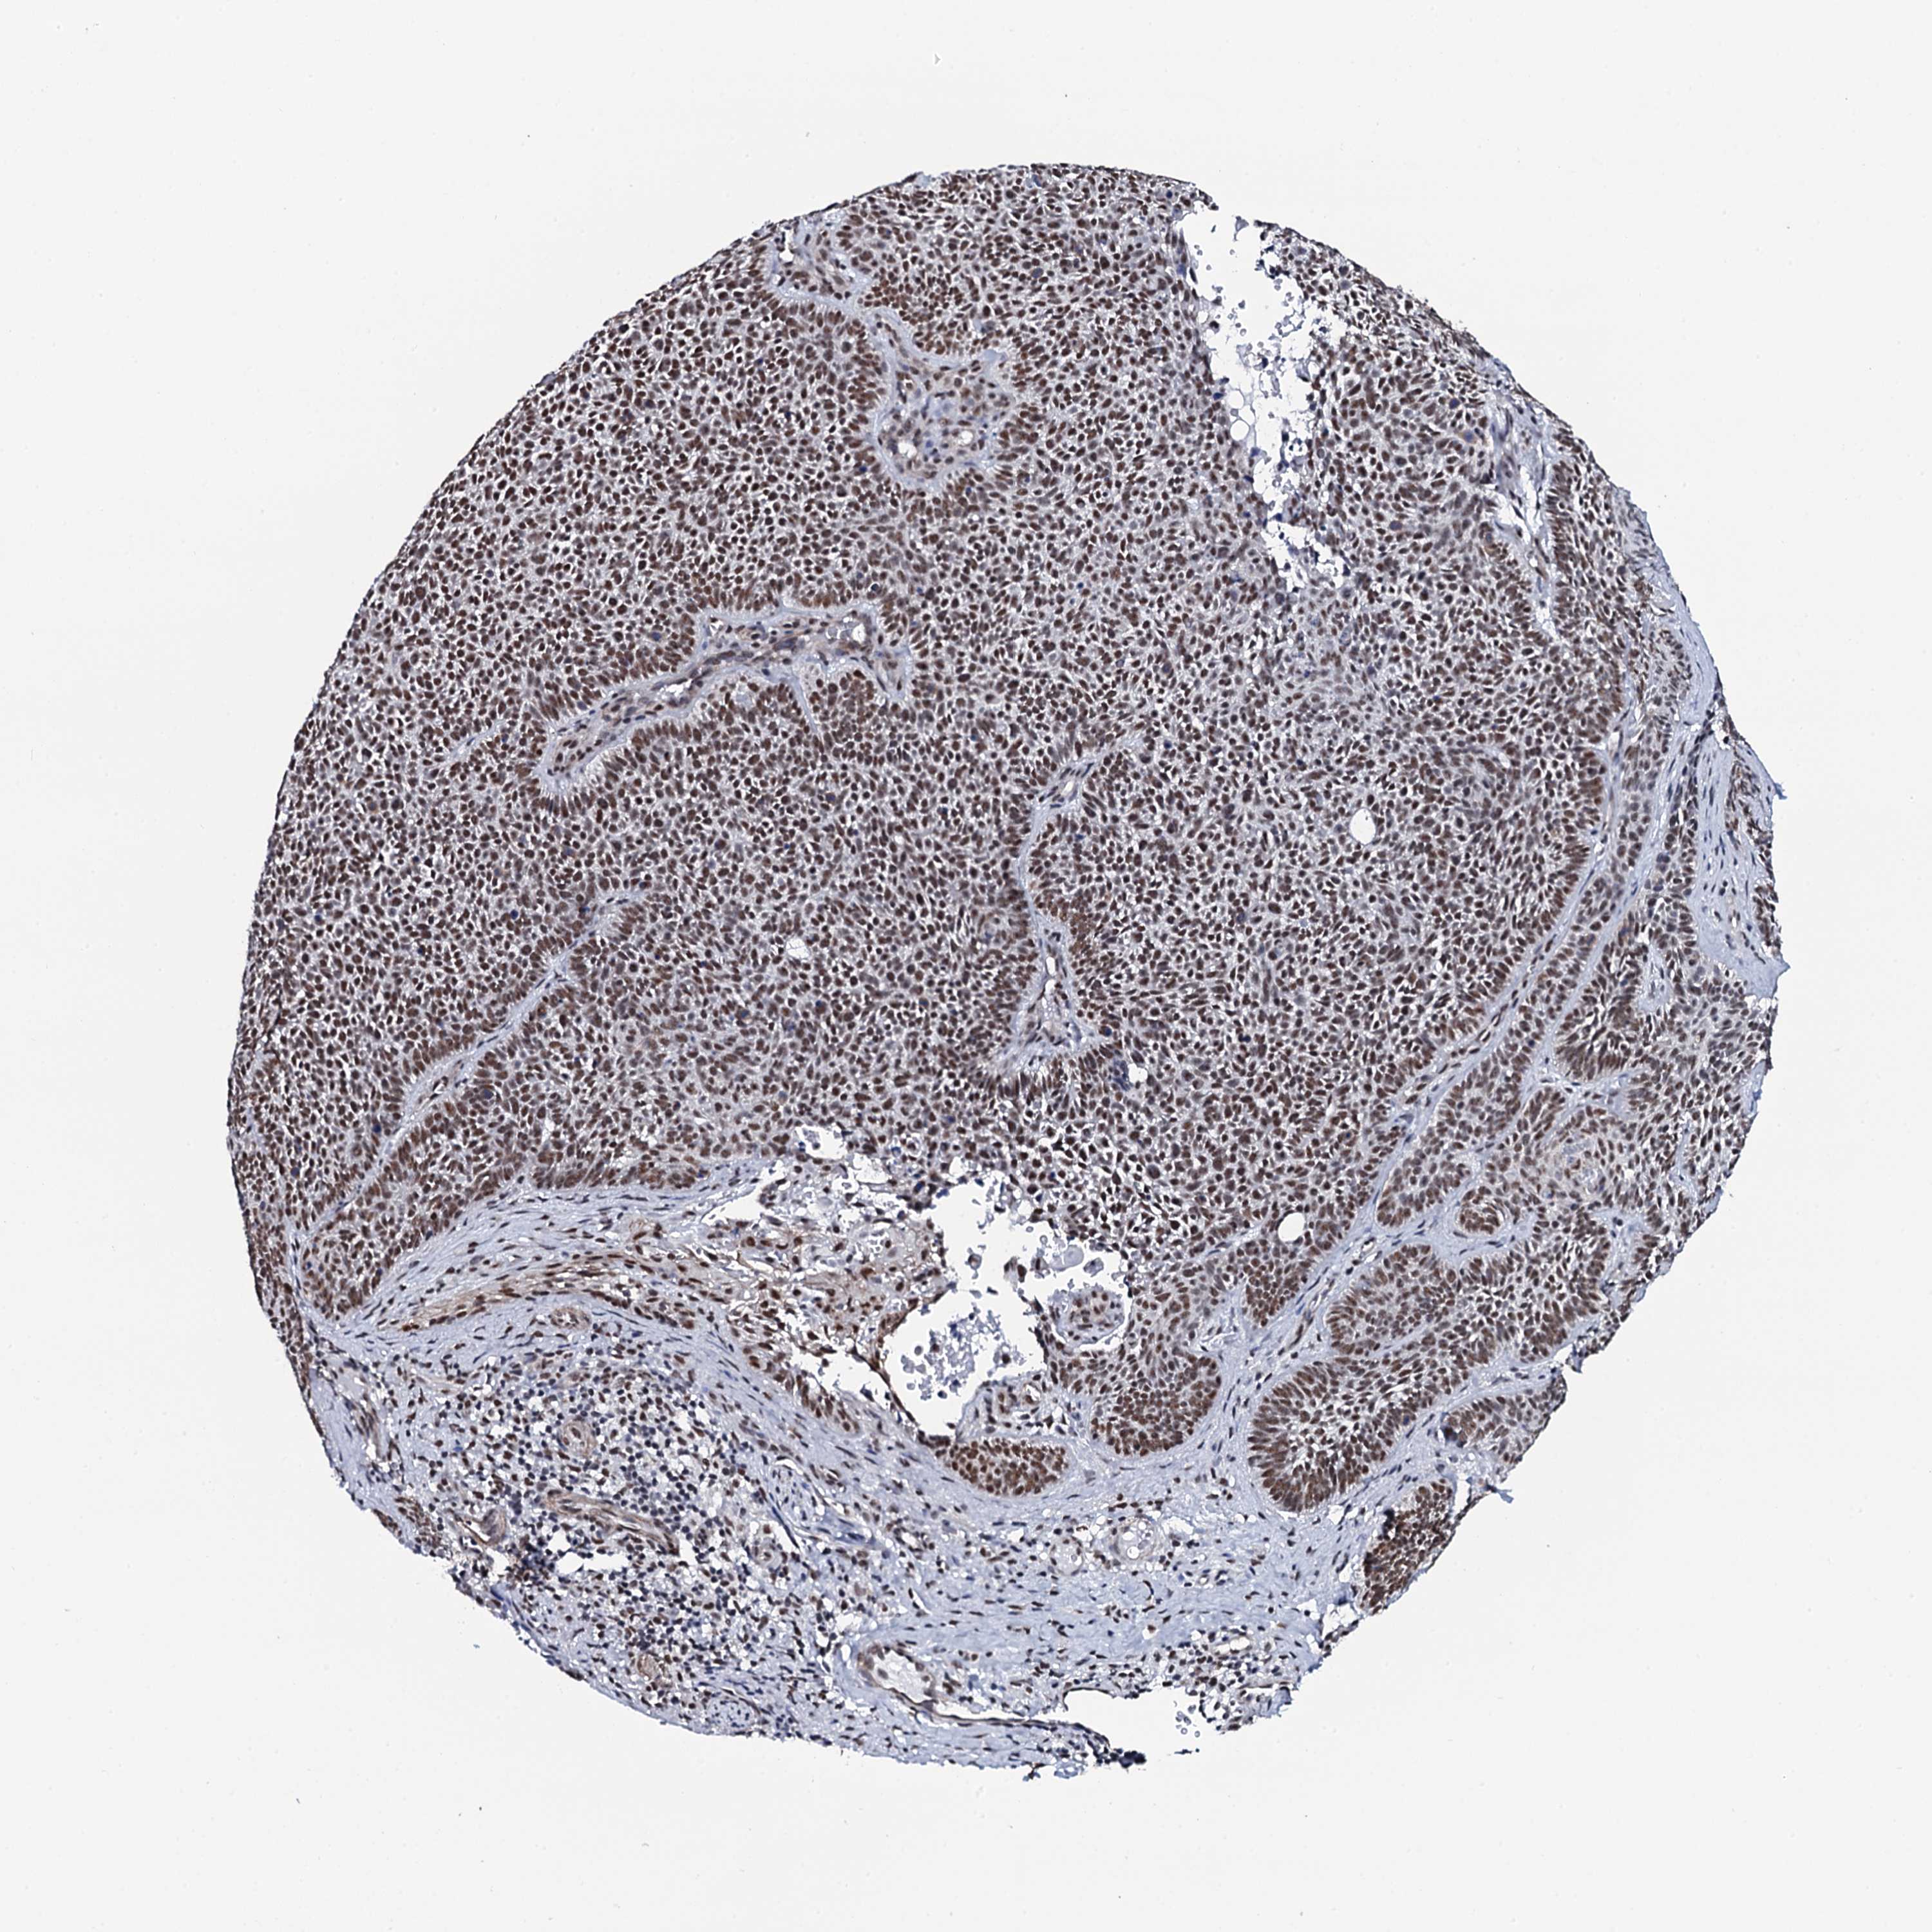

Basal cell and squamous cell cancer

SKIN CANCER - Protein expressioni

A mouse-over function shows sample information and annotation data. Click on an image to view it in a full screen mode. Samples can be filtered based on level of antibody staining by selecting one or several of the following categories: high, medium, low and not detected. The assay and annotation is described here.

Antibody stainingi

Antibody staining in the annotated cell types in the current human tissue is reported as not detected, low, medium, or high, based on conventional immunohistochemistry profiling in selected tissues. This score is based on the combination of the staining intensity and fraction of stained cells.

Each image is clickable and will lead to virtual microscopy that enables deeper exploration of all samples and also displays staining intensity scores, fraction scores and subcellular localization as well as patient and tissue information for each sample.

Antibody HPA039878

Staining

High

Medium

Low

Not detected

Intensity

Strong

Moderate

Weak

Negative

Quantity

>75%

75%-25%

<25%

None

Location

Nuclear

Cytoplasmic/membranous

Cytoplasmic/membranous,nuclear

Squamous cell carcinoma, NOS